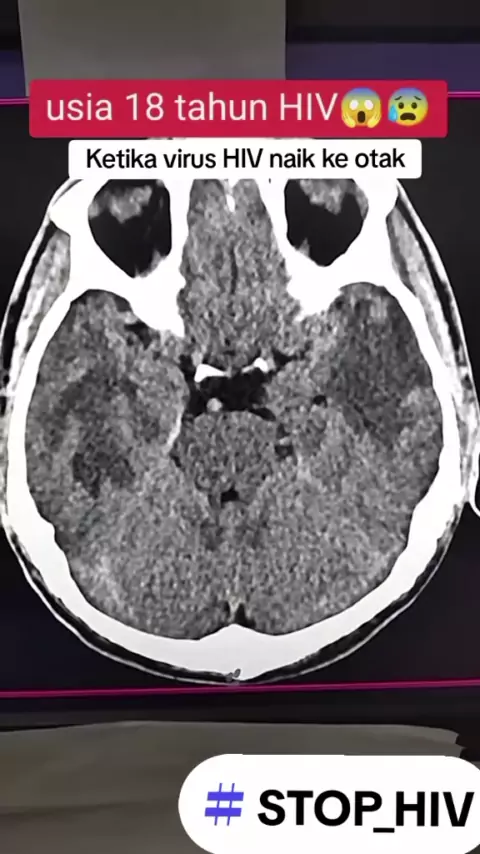

waspadalah ketika virus hiv sudah menyerang otak ya...

ingin hidupmu berakhir seperti ini ?? silahkan remehkan hiv 😵‍💫😵‍💫😵‍💫😵‍💫😵‍💫🥸🥸🥵🥵🥵🥵